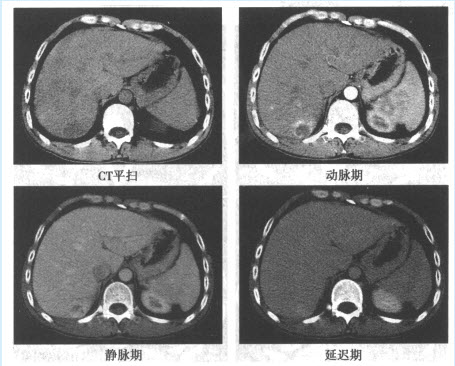

患者,男,45岁。体检时发现肝右后叶见一稍强回声光团,行CT平扫及增强检查。

该病的增强扫描的影像特点是()